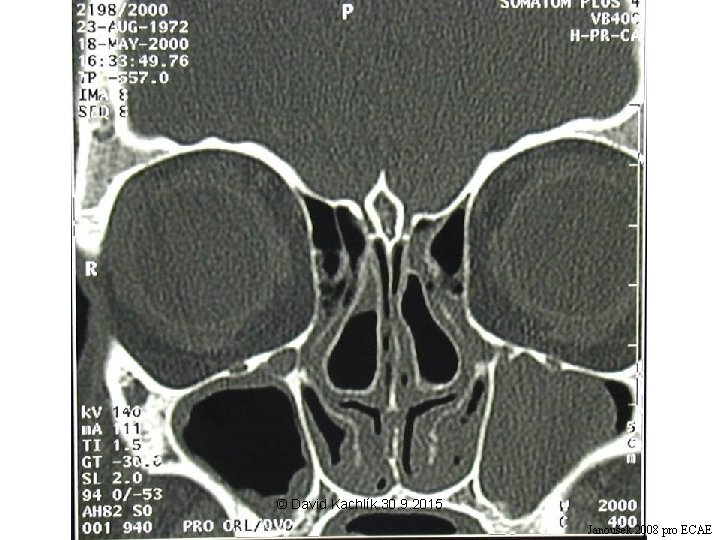

X-ray of paranasal sinuses © David Kachlík 30. 9. 2015

Nasal cavity + PS – clinical notes • epistaxis (bleeding from the nose) - locus Kiesselbachi, plexus Woodruffi, a. sphenopalatina • liquorrhea (the flow of the cerebrospinal fluid from the nose) – fractures of the base of the skull • sinusitis – puncture through the nasal cavity (for s. maxillaris at the level of the inferior nasal meatus – inferior antrotomy) – suction – FES (= functional endonasal surgery) • surgical approach to hypophysis through sinus sphenoidalis • sinus maxillaris – teeth • cellulae ethmoidales – orbit • examination: rhinoscopy (anterior, posterior), diaphanoscopy, X-ray, CT © David Kachlík 30. 9. 2015